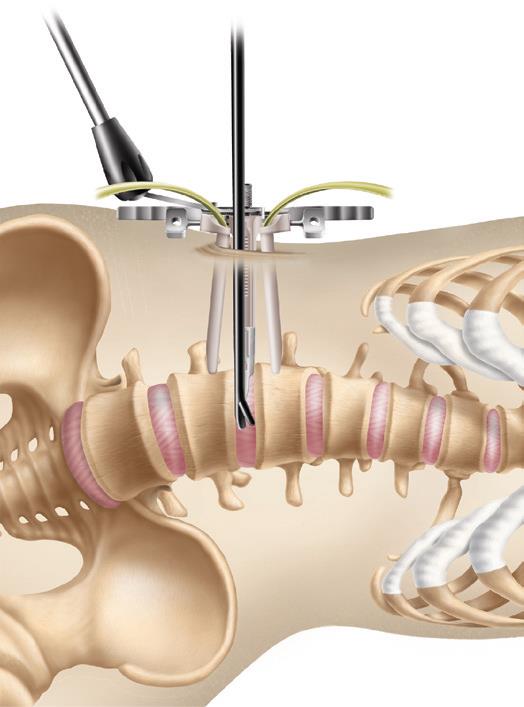

La intervención se realiza con el paciente anestesiado y colocado de lado, y con una pequeña incisión en el costado a la altura del espacio que queremos intervenir, y con la ayuda del aparato de Rayos X se localiza el espacio a intervenir (Fig 2).

Se realiza disección roma, separación de las estructuras con torundas, y especial cuidado, para evitar lesionar estructuras.

Se deja el peritoneo por delante de la columna vertebral. El psoas queda en la parte lateral de la columna, y hay que entrar entre sus fibras, intentado separarlo hacia posterior.

Posteriormente con la ayuda de un separador especial (Fig 3) y de instrumentos específicos, se reseca el disco intervertebral con el fin de colocar cajas rellenas de injerto en lugar de los discos que se han quitado y conseguir con esto diferentes funciones una separación de las vertebrales y por tanto un aumento del canal espinal y de los forámenes por los que salen las estructuras nerviosas, con lo que se consigue una descompresión de los elementos nerviosos (descompresión indirecta) (Fig 4).